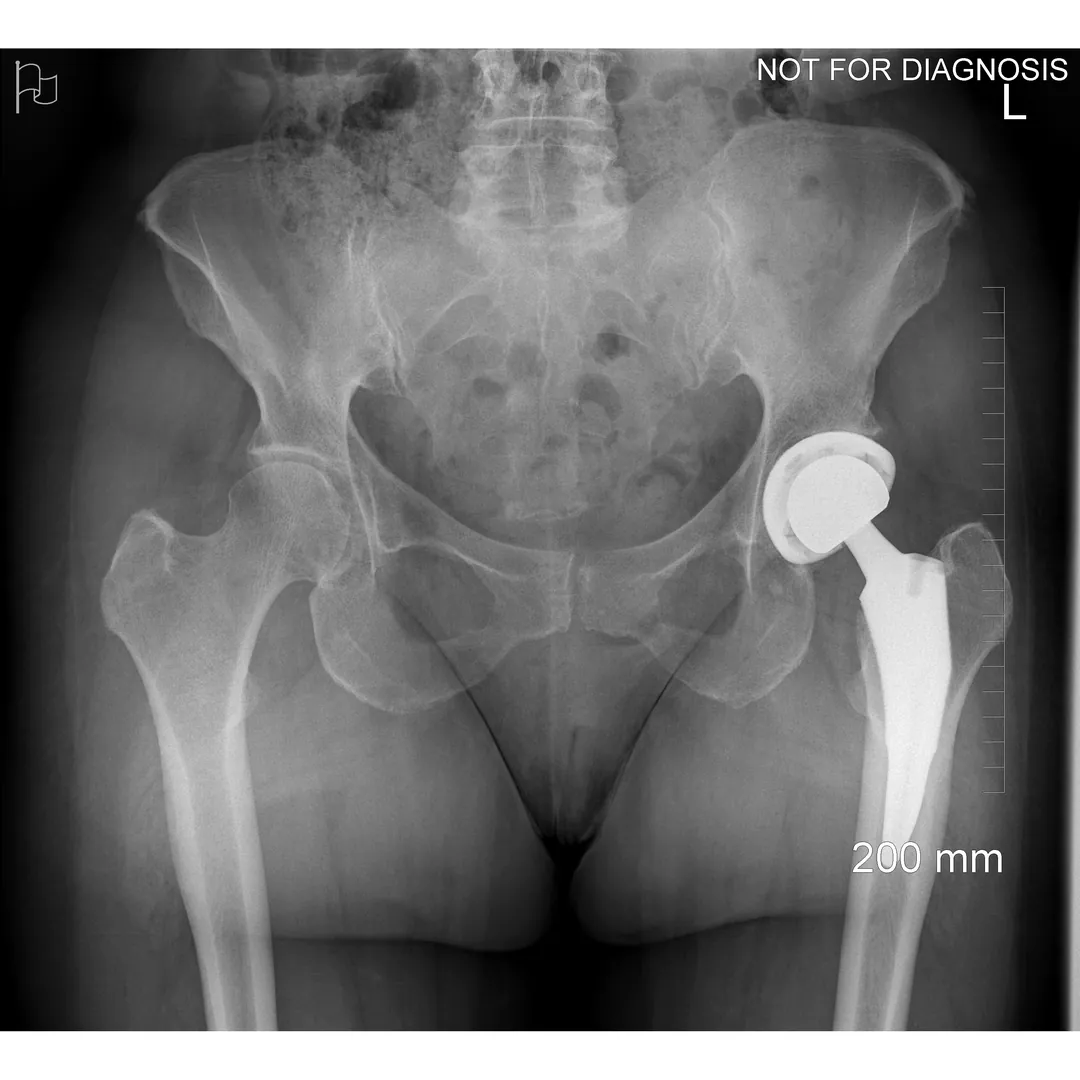

A total hip replacement (also called total hip arthroplasty) is a surgical procedure in which a damaged or worn hip joint is replaced with artificial components. The hip is a ball-and-socket joint, meaning the ball at the top of the thigh bone sits in a socket on the pelvis. During surgery, the damaged ball (femoral head) is replaced with a metal or ceramic ball attached to a stem, and the damaged socket is replaced with a metal cup lined with plastic, ceramic, or metal.

- The surgeon removes the damaged bone and cartilage and inserts the artificial joint